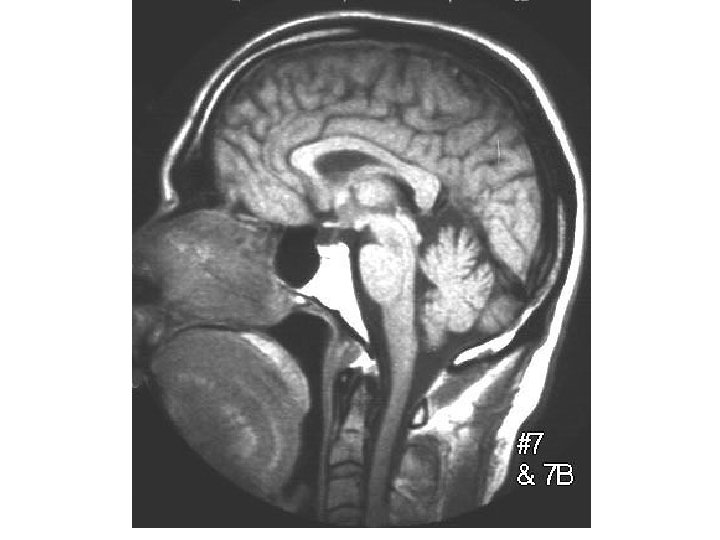

14 points 1. Frontal (anterior) horn of Lateral ventricle 2. Body (central part) of

14 points 1. Frontal (anterior) horn of Lateral ventricle 2. Body (central part) of lateral ventricle 1 3. Trigone of lateral ventricle (not in Netter) 6 4. Occipital (posterior) horn of lateral ventricle 7 5. Temporal (inferior) horn of lateral ventricle 6. Interventricular foramen (of Monro) 7. Interthalamic adhesion 8. 3 rd ventricle 9. Cerebral aqueduct (of Sylvius)* 10. 4 th ventricle 11. Foramen of Luschka 12. Lateral recess 13. Median aperture (Foramen of Magendie) 14. Central canal of spinal cord See plate 102 -103 2 8 3 9 4 5 10 11 12 13 Ventricular System Drawing 14